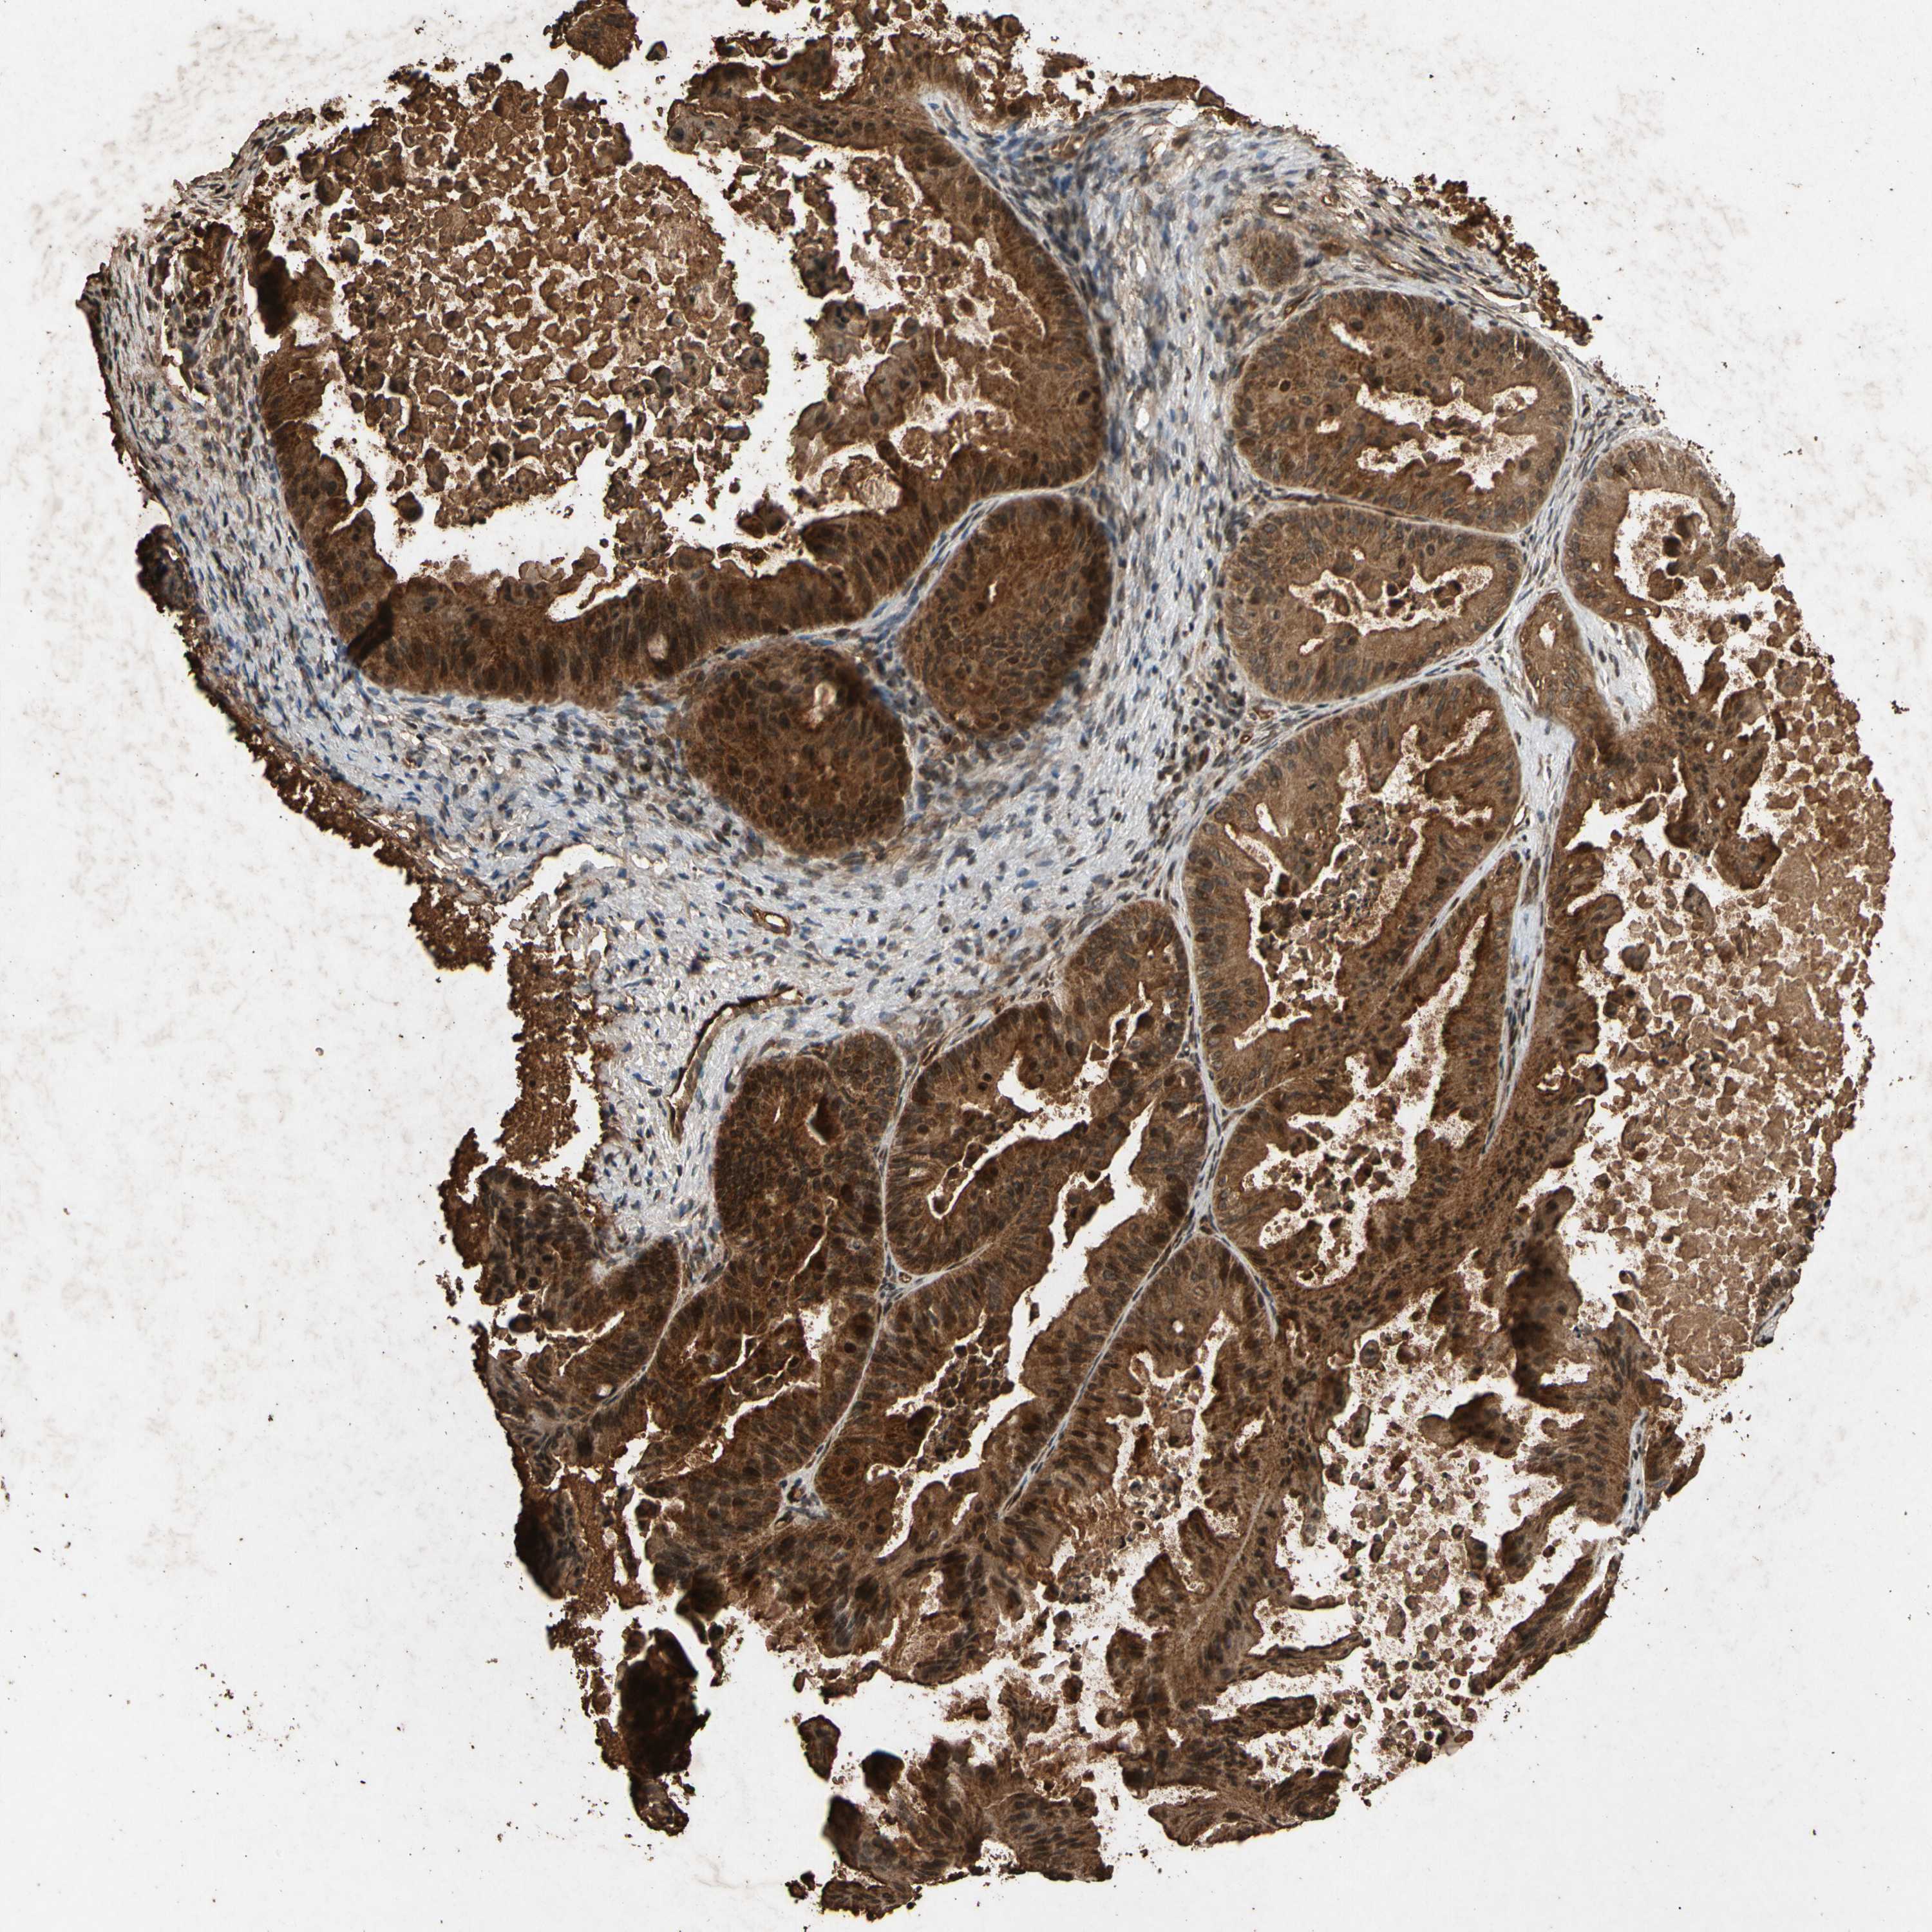

OVARIAN CANCER - Protein expressioni

A mouse-over function shows sample information and annotation data. Click on an image to view it in a full screen mode. Samples can be filtered based on level of antibody staining by selecting one or several of the following categories: high, medium, low and not detected. The assay and annotation is described here.

Note that samples used for immunohistochemistry by the Human Protein Atlas do not correspond to samples in the TCGA dataset.

Antibody stainingi

Antibody staining in the annotated cell types in the current human tissue is reported as not detected, low, medium, or high, based on conventional immunohistochemistry profiling in selected tissues. This score is based on the combination of the staining intensity and fraction of stained cells.

Each image is clickable and will lead to virtual microscopy that enables deeper exploration of all samples and also displays staining intensity scores, fraction scores and subcellular localization as well as patient and tissue information for each sample.

Antibody CAB008681

Cystadenocarcinoma, mucinous, NOS

Carcinoma, endometroid

Cystadenocarcinoma, serous, NOS

Carcinoma, NOS